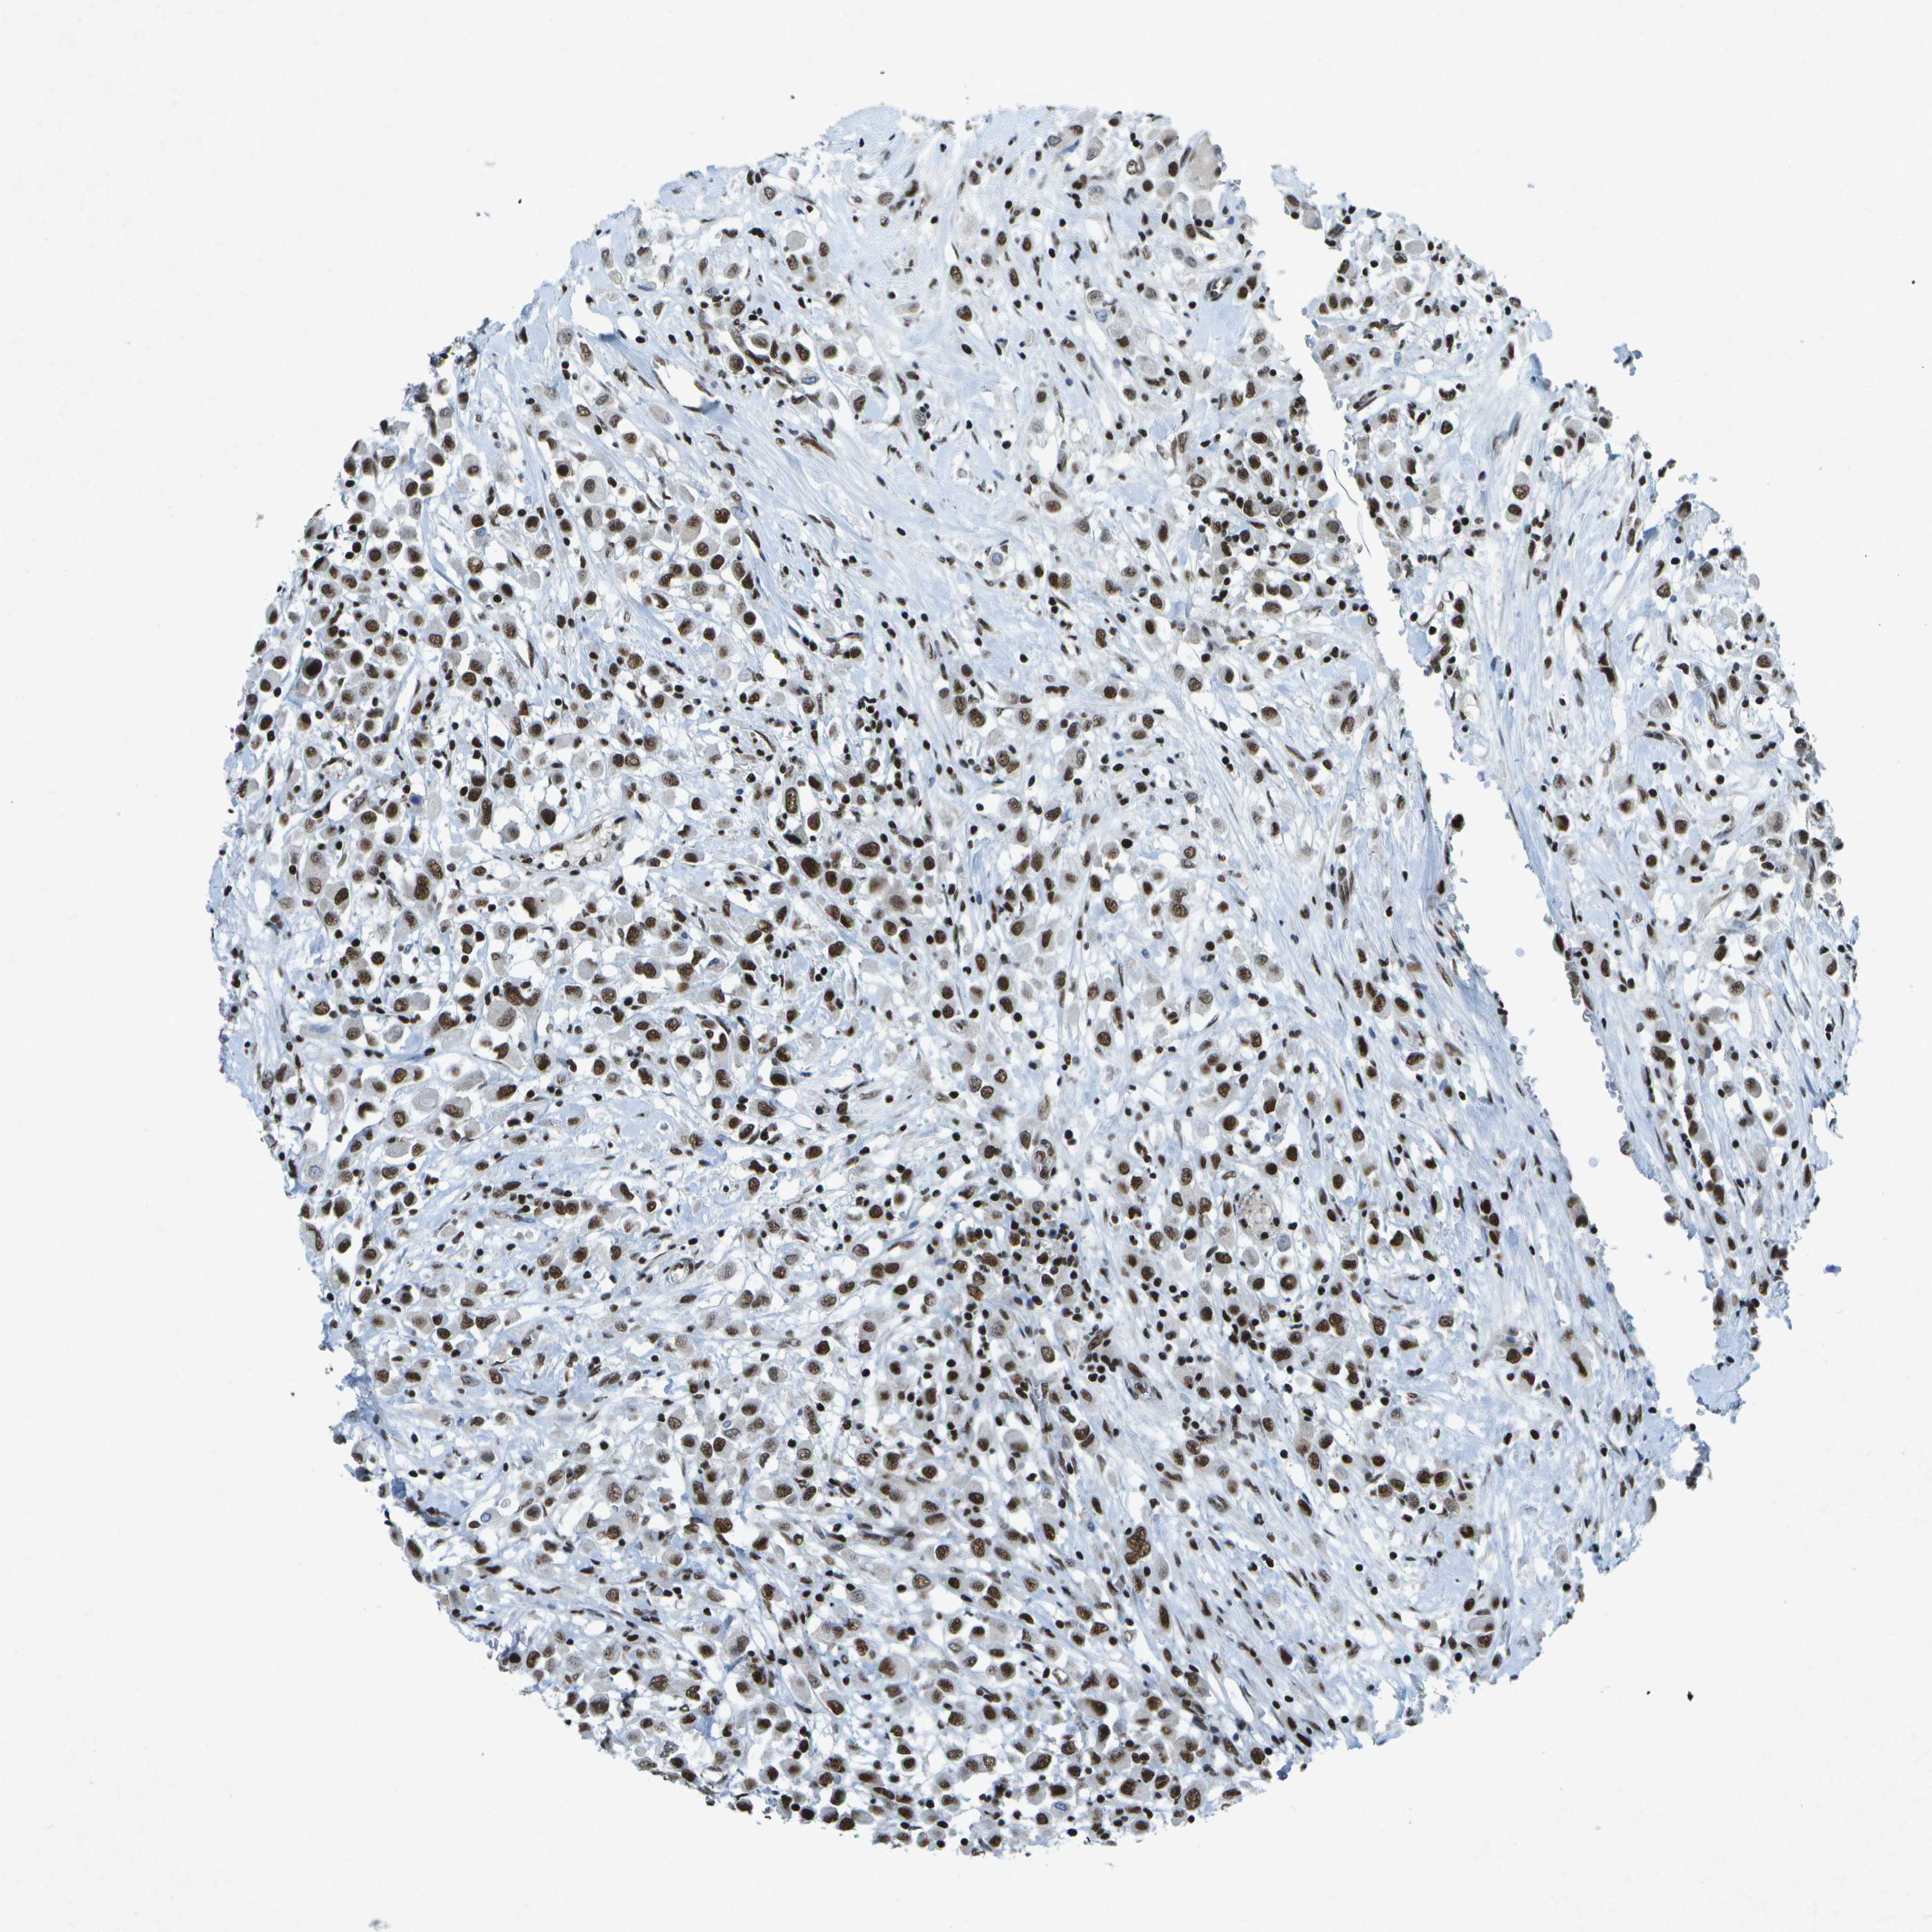

CANCER BREAST CANCER Show tissue menu

BRCA TCGA BRCA VALIDATION PROTEIN EXPRESSION

ANTIBODIES

AND

VALIDATION